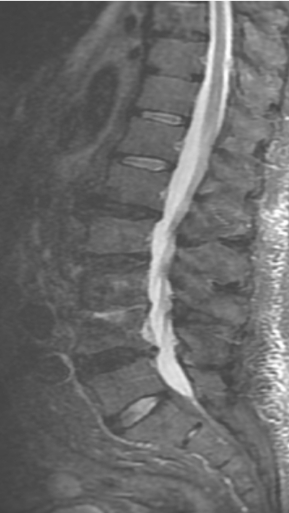

Грыжа Диска L4-L5

3 процедуры ФДТ, 9 процедур MBST

Параметры изменяются в зависимости от процедуры

Дата публикации: 22.08.2025 14:27:20

Спондилодисцит L3 – L4

4 процедуры ФДТ, 9 процедур MBST, 20 процедур ИПМТ

Дата публикации: 22.08.2025 14:27:12